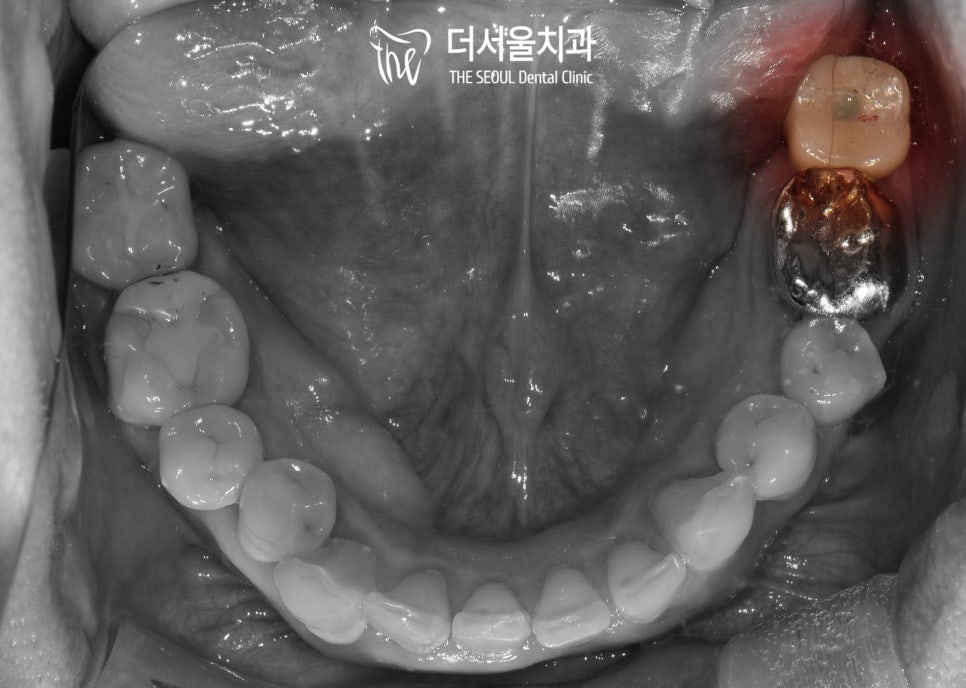

* 육안 관찰

저~ 뒤쪽으로 빼꼼 머리를 내밀고 있는

사랑니 가 관찰되었습니다.

옆으로 누워있었는데요.

이런 모습을 갖고 있는 것들은

말썽을 일으킬 확률이 매. 우. 높습니다.